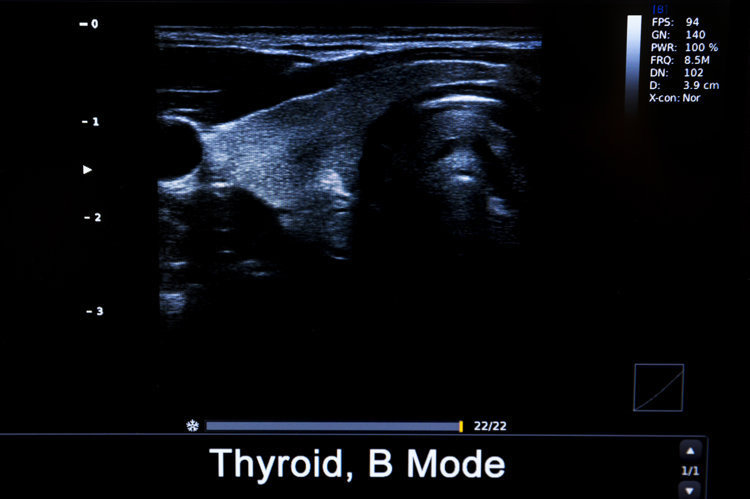

• 甲状腺结节

甲状腺结节是指甲状腺组织内出现的局限性肿块,会跟着吞咽当作高下出动。

中国医学科学院肿瘤病院山西病院头颈外科主任李德志示意,B超查验中有20~30%的东说念主会检出大小不一的甲状腺结节,大部分为良性,最终会诊为恶性的概率仅有3~4%。但还是提议鄙俗东说念主每年进行一次甲状腺查验。